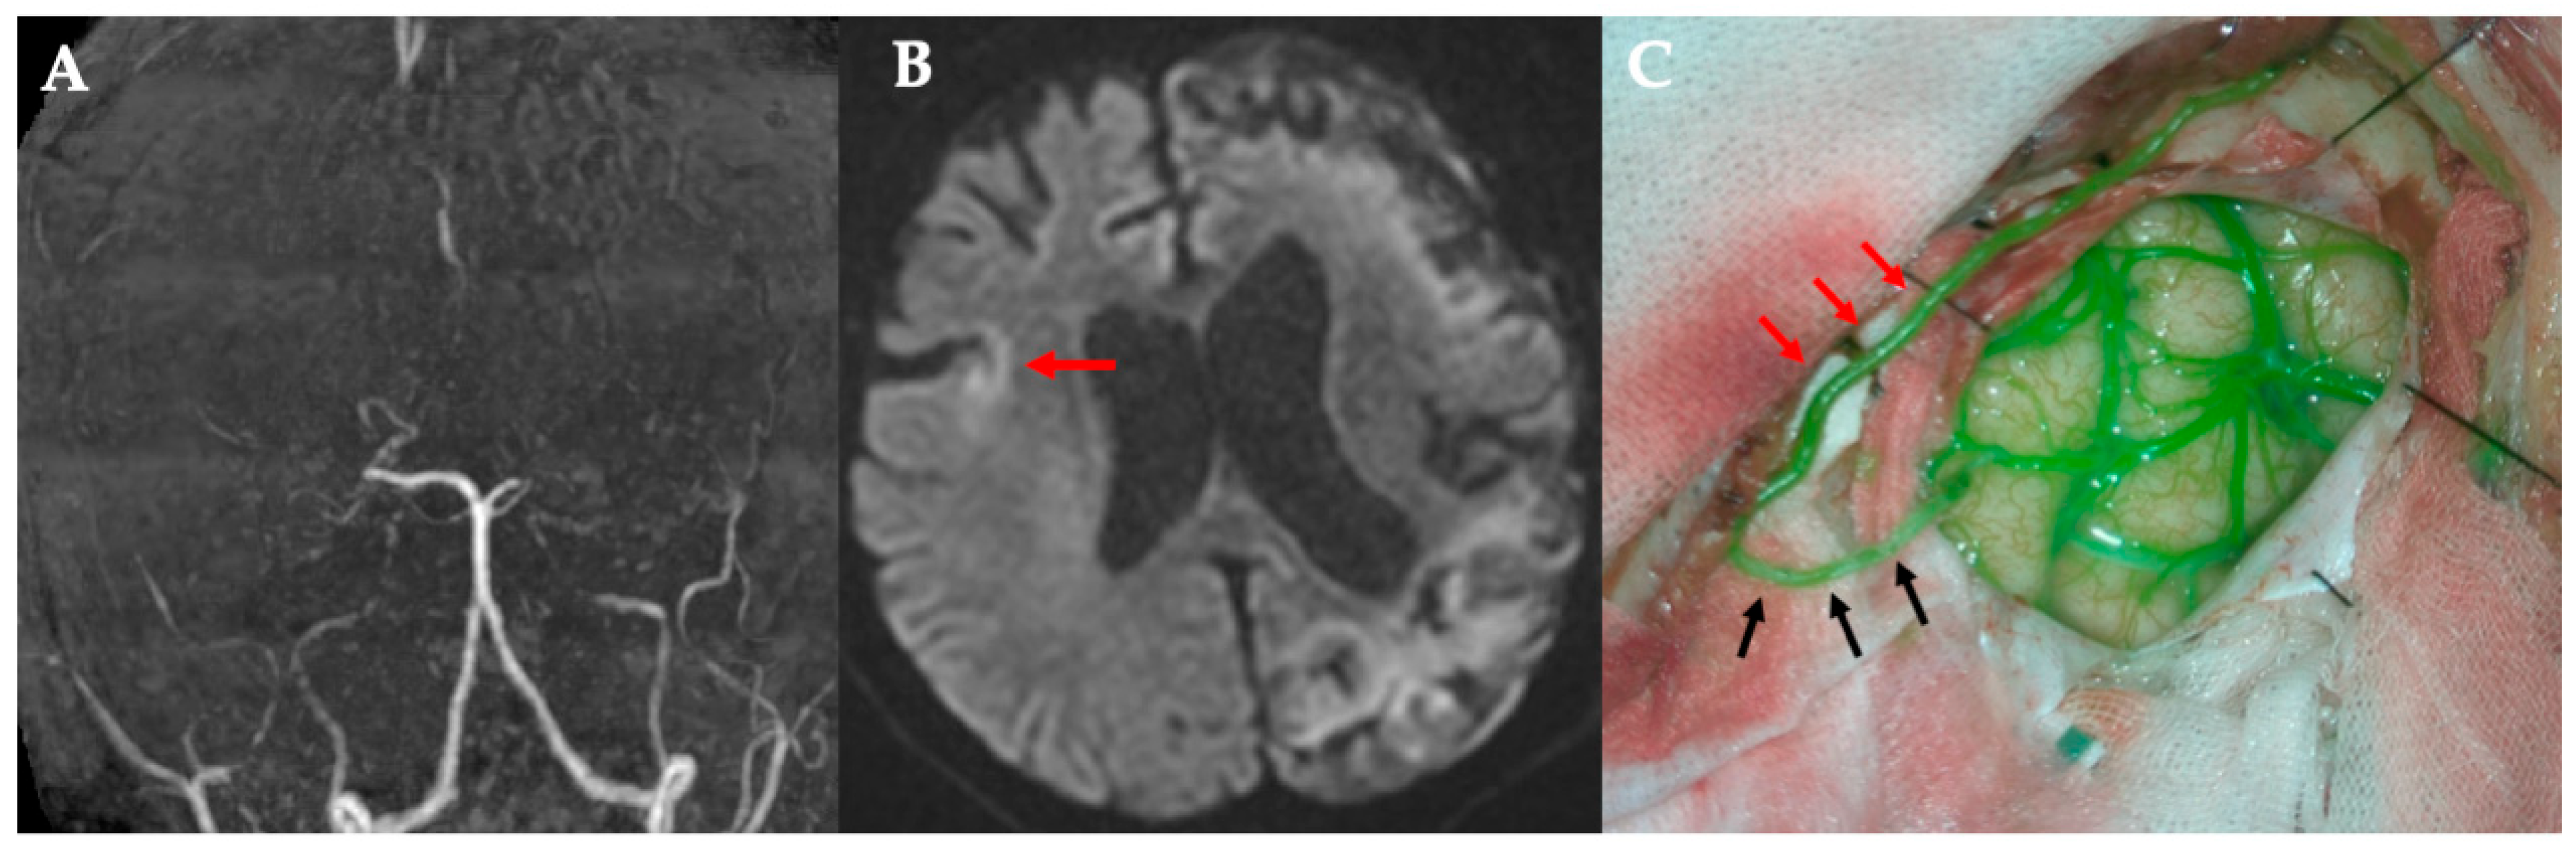

All five procedures were technically successful. Table 1 summarizes the key characteristics of each case. Preserving a side branch added an average of 5.6 min to the procedure (range, 3–11 min). In all cases, the bypass was patent on intraoperative ICG angiography, which demonstrated immediate perfusion of the distal MCA territory through the graft (Figure 2 and Figure 3). A schematic of this procedure is shown in Figure 4. The caliber of the STA side-branch donors ranged from approximately 0.5 mm to 1.1 mm (mean: 0.88 mm), closely matching the recipient artery diameters (0.4–0.9 mm, mean: 0.64 mm). No intraoperative complications (such as anastomotic thrombosis and vessel injury) occurred. The main STA trunk and any unused branches remained in situ to continue perfusing the scalp, and no signs of scalp ischemia were observed after sacrificing the side branch.

Figure 4. Case 1. Scheme of modified STA-MCA bypass using STA side-branch donors. STA, superficial temporal artery; MCA, middle cerebral artery.